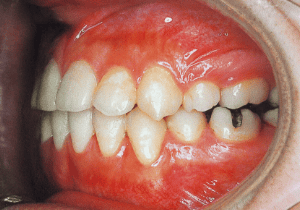

1 At start of treatment 7-21-’88

2 After treatment 2-10-’99

A case of diverted and cross bite during the deciduous dentition. Despite early treatment, the deviation progressively worsened with age, necessitating surgical treatment. At the initial visit, the patient had a deciduous dentition, and observation was planned (3). With the eruption of the permanent incisors, the mandible shifted slightly to the right, resulting in a cross bite (1) At this point, asymmetry can be confirmed in the front view. However, it is slight. The cephalometric X-ray reveals a structure with a slightly dominant mandible, but asymmetry in the mandibular ramus is not observed.

On the lateral cephalometric radiograph, the vertical height of the face appears greater than its depth. The lower facial height is also high, suggesting a shape somewhat prone to developing a protruding lower bite, though this does not raise significant concern (6). The facial photograph of front view shows slight asymmetry in the face, but it is not particularly extreme (1). The first phase of treatment corrected the anterior cross bite and deviation, but subsequent growth exacerbated the mandibular deviation, necessitating surgical treatment.